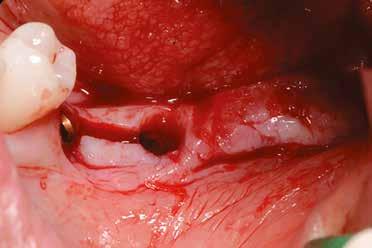

Szeretnék mutatni néhány ábrát az egyik bonyolult esetről, a közelmúltból. A CT-n látszik, hogy a három gyökér teljesen „körbenőtte” az ideget. Van olyan frontális metszeti kép, ahol csak a gyökerek vannak a nervus körül, ezen a szakaszon egyáltalán nincs meg a csontos fala a canalisnak. Szeparációs technikával, viszonylag könnyen, minimális traumával, szövődménymentesen sikerült eltávolítani a fog minden részét. A várakozásnak megfelelően, a beteg nem számolt be paraesthesiáról.

Alapos kivizsgálással, részletes tervezéssel, óvatos műtéti technikával még ilyen, extrém esetekben is sikeresen, szövődménymentesen meg lehet oldani a komplikált helyzeteket. Jobb lenne azonban, ha a műtét időpontjának helyes megválasztásával elkerülhetőek lennének ezek a magas rizikójú beavatkozások.